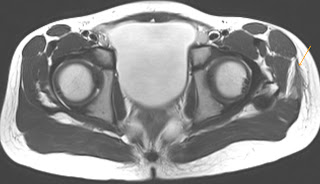

24 years young male complains of severe pain in right testis since two days.

USG shows hypoechoic lesion near lower pole. MRI was done.

what do you think is the diagnosis..?

Let us see the findings first.

arrow points to a triangular hypointensity.

arrows point to a triangular hypointensity.

an area of facilitated diffusion seen in lower pole of right testis.

T1 contrast and in particular subtraction image shows area of lack of enhancement surrounded by well enhancing rim.

These findings with history of pain are consistent with segmental testicular infarct.

what are radiological findings of segmental testicular infarction.

It is characterised by presence of a triangular shaped avascular intrataesticular lesion on sonography or MRI and enhancement of surrounding borders on MRI.

how do you differentiate it from testicular tumor.

triangular shape , lack of vascularity , clinical setting of severe pain are differenital features of segmental infarct. follow up should be advised.